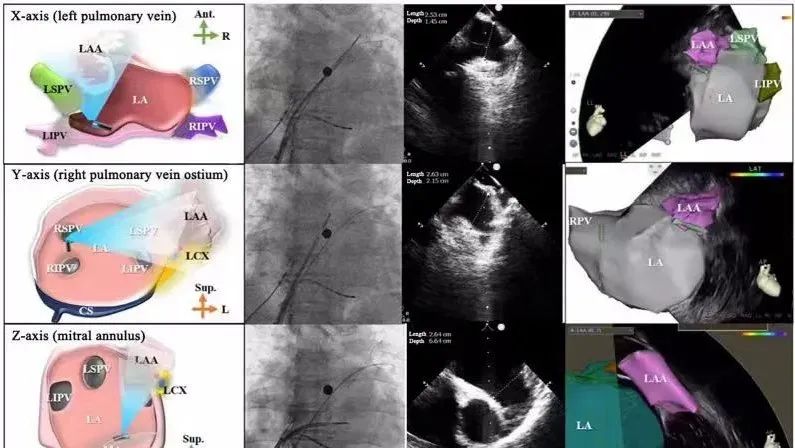

一種與心導(dǎo)管檢查相結(jié)合的超聲心動圖診斷新興技術(shù),通過將超聲探頭置于心腔內(nèi)部,發(fā)射并接收超聲信號,來精確獲取心臟解剖結(jié)構(gòu)、心臟血流動力學(xué)等信息的實(shí)時成像。與其他影像技術(shù)相比,ICE技術(shù)具有操作簡單、無輻射、安全性高、手術(shù)效率高、實(shí)用等優(yōu)勢,ICE在很大程度上有望取代經(jīng)食道超聲心動圖(TEE),成為電生理和結(jié)構(gòu)性心臟病領(lǐng)域的理想成像方式。

目前ICE技術(shù)已被應(yīng)用于左心耳封堵、房顫射頻消融、二尖瓣成形、房間隔缺損封堵等多種心臟介入手術(shù),應(yīng)用場景主要圍繞臟電生理、結(jié)構(gòu)性心臟病等領(lǐng)域,目前以電生理應(yīng)用為主。數(shù)據(jù)顯示,我國結(jié)構(gòu)性心臟病介入器械市場規(guī)模已從2017年的4億元增長至2021年的20億元,年復(fù)合增長率達(dá)48.3%;預(yù)計到2025年,該市場規(guī)模將達(dá)到104億元,可以預(yù)見ICE市場規(guī)模也將同步高速增長,未來市場發(fā)展空間廣闊。

心腔內(nèi)超聲(ICE)技術(shù)壁壘極高,國內(nèi)主要廠商核心部件仍舊為進(jìn)口,集成了超聲和圖像處理最前端技術(shù),包括超聲探頭、線纜、軟件成像算法等,是當(dāng)前內(nèi)窺超聲方向最具挑戰(zhàn)的領(lǐng)域。ICE的應(yīng)用經(jīng)歷了2D平面成像、3D三維立體成像、以及4D的實(shí)時三維立體成像階段。